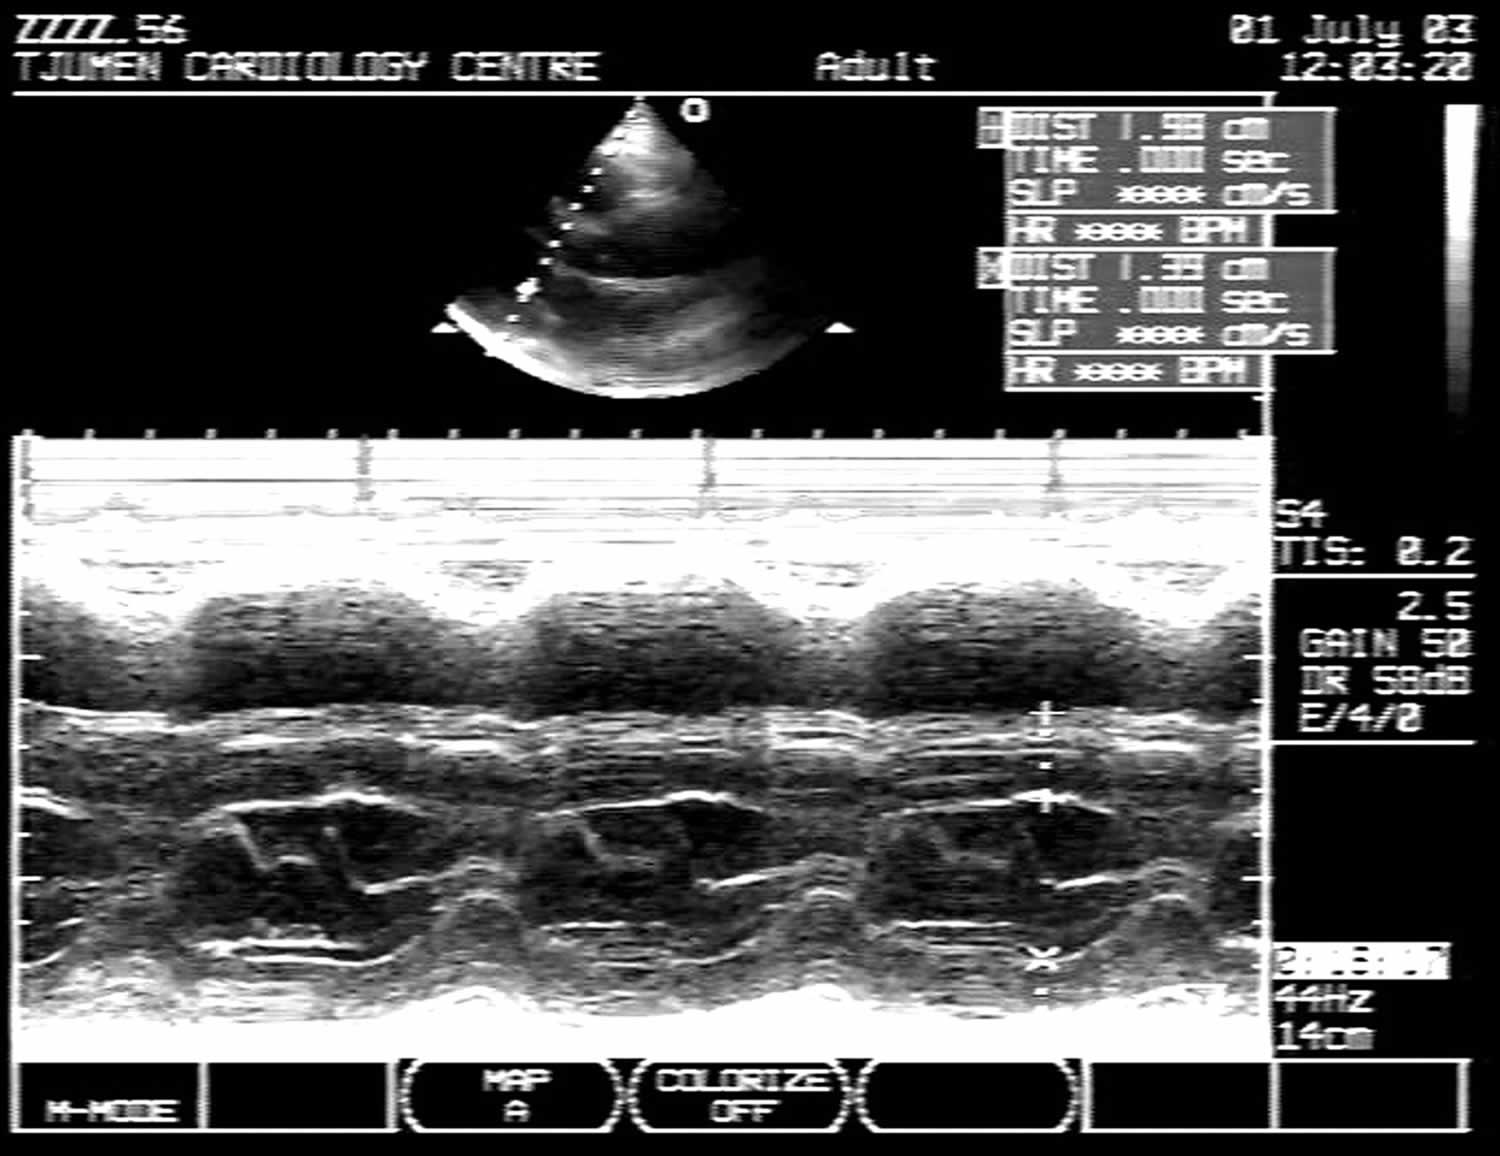

Web asymmetric septal hypertrophy (defined by an echocardiographic interventricular septum to left ventricular free wall thickness ratio of greater than or equal to 1.3 and by the presence. Web asymmetric septal hypertrophy (n.). Ash means asymmetrical septal hypertrophy.

Web asymmetric septal hypertrophy (defined by an echocardiographic interventricular septum to left ventricular free wall thickness ratio of greater than or equal to 1.3 and by the presence. Web left ventricular hypertrophy is thickening of the walls of the lower left heart chamber. Web hypertrophic cardiomyopathy with an asymmetrical pattern of hypertrophy, with a predilection for the interventricular septum and myocyte disarray.